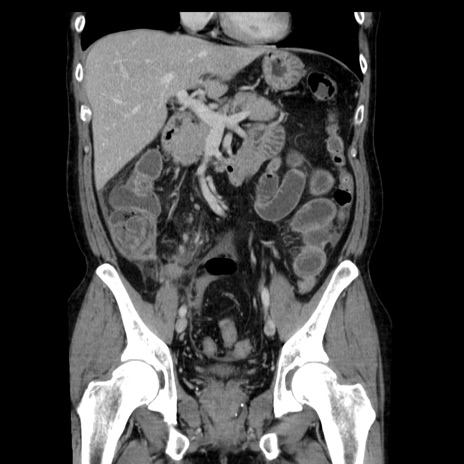

症例29(冠状断像)

【症例】40歳代男性

【現病歴】2日前から胃痛あり。徐々に周期的な激痛に変化した。本日になっても激痛があるため受診。

【身体所見】意識清明、BT 38-39℃台あり、腹部:膨満、やや硬、右下腹部に圧痛あり。

【データ】WBC 8500、CRP 23.26